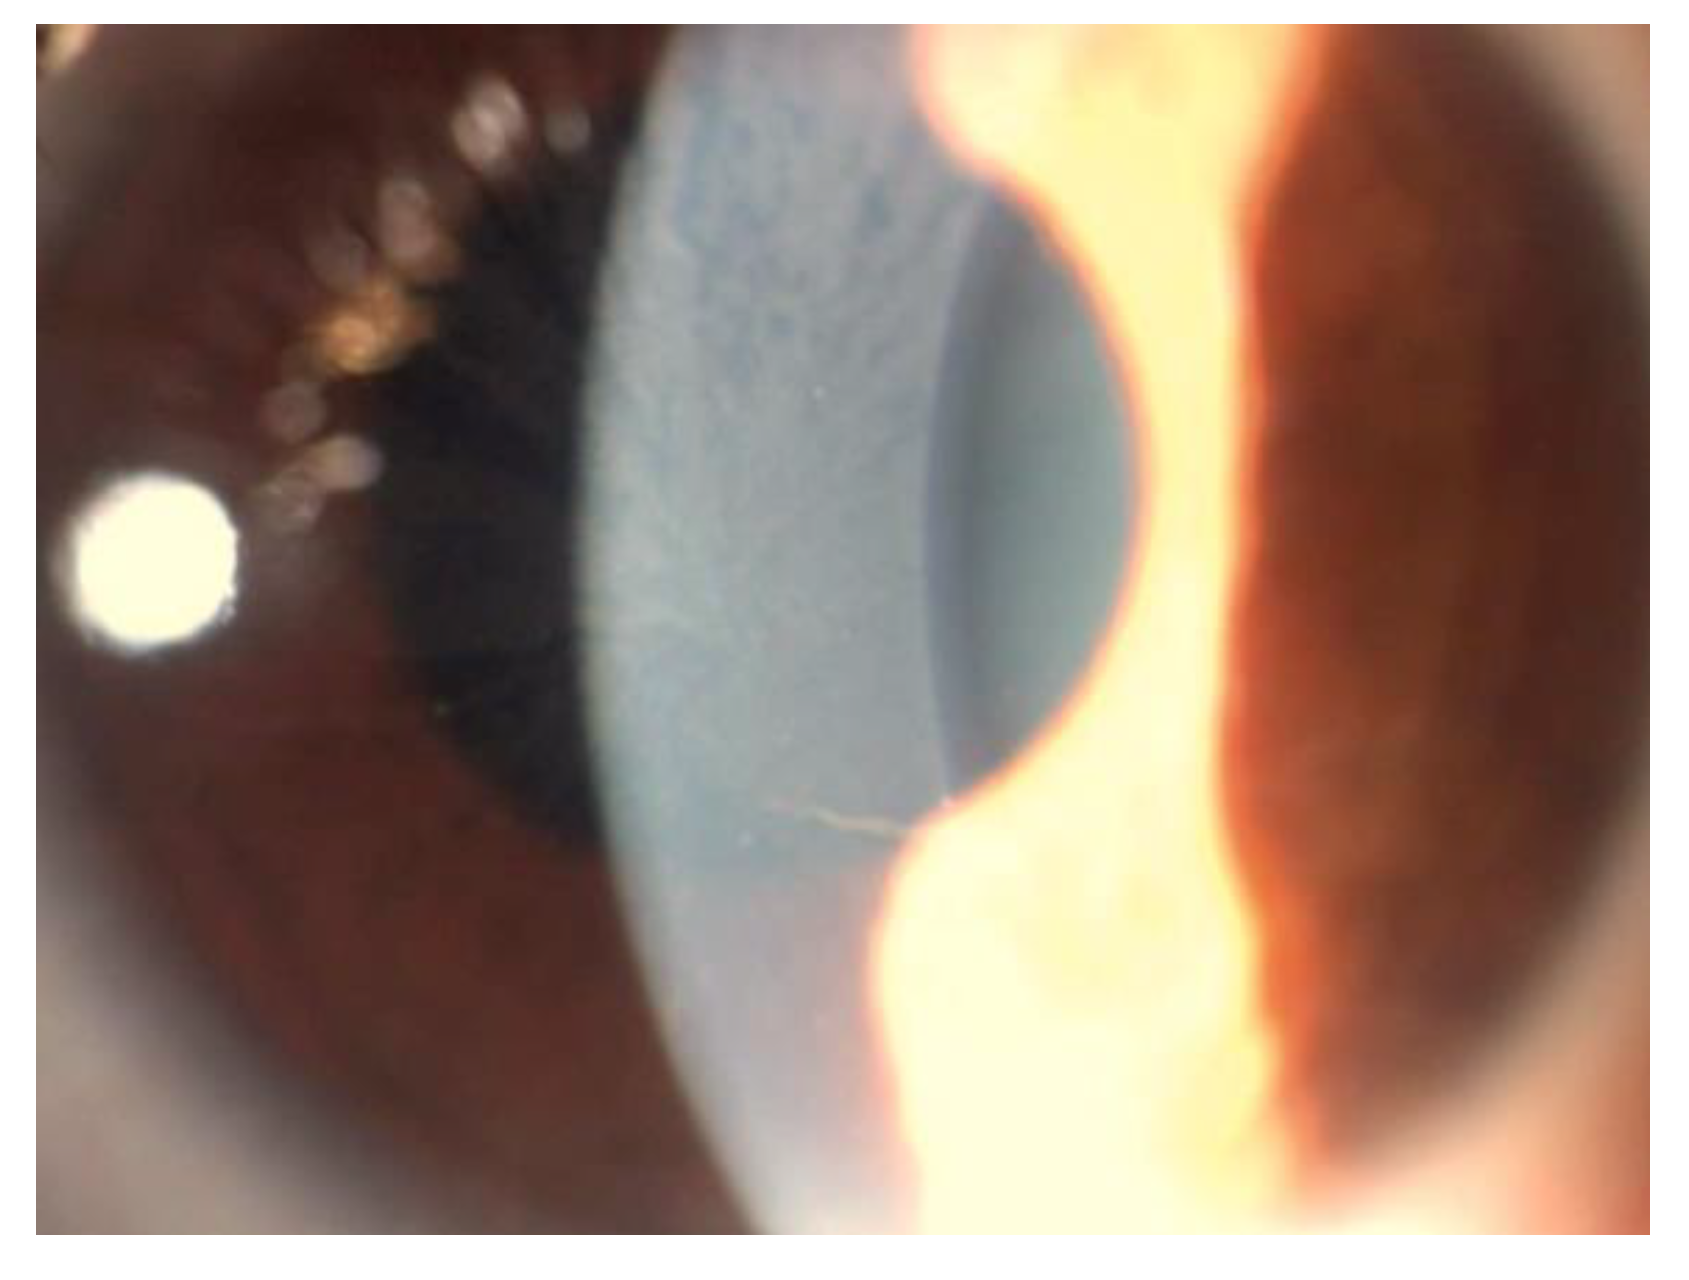

5. Corneal Manifestations

5.5. Differential Diagnosis of Vortex Keratopathy